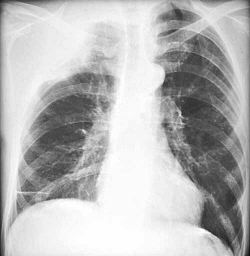

Refer to this picture for question 1.

1. Related features include:

Refer to this picture for question 2.

2. Blood films related to the above appearance include: